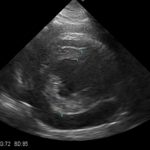

9歳の柴犬が散歩中に突然倒れる事があるとのことでかかりつけを受診しました。幼少時よりてんかん発作を発症する事があるが、今回の様子はてんかんの時とは異なる様だとのことで精査を希望され来院しました。心音は微弱でマッフルを呈していました。また、腹水の貯留も確認されました。心臓超音波検査では心膜液の貯留が確認されました。心嚢水の除去を行なったところ、出血性の心嚢水でした。数日間は心嚢水の除去のみで一般状態は改善していました。しかし、再発すると虚脱するといった症状が確認されたため、再発性の心タンポナーゼを回避するために、胸腔鏡下で心膜切除術を実施しました。同時に中皮腫、血管肉腫、特発性との鑑別にCTによる精査も実施しております。心膜の病理検査では腫瘍性の変化はなく、著しく繊維化した心膜であり、特発性と診断されました。胸腔鏡下での手術であったため、数日間の入院で痛みも少なく良好に経過しています。